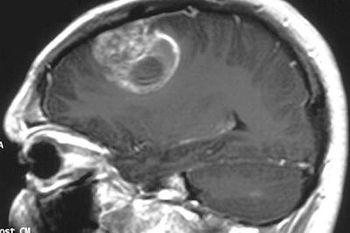

Manmeet Ahluwalia, MD, Head of Operations in the Brain Tumor Center at Cleveland Clinic, explains what a team approach should look like when treating brain tumors and other rare cancers.

Manmeet Ahluwalia, MD, Head of Operations in the Brain Tumor Center at Cleveland Clinic, discusses the importance of team approaches when treating brain tumors and other rare cancers.